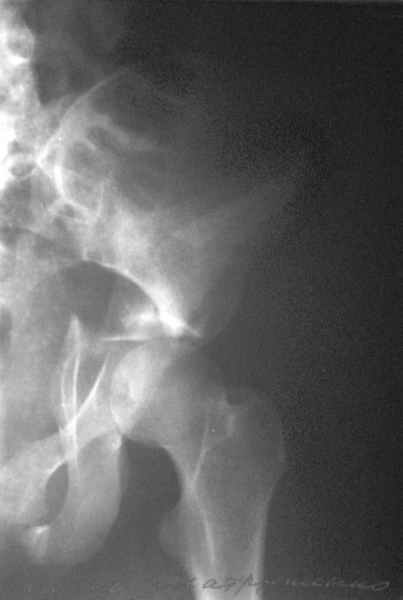

Посылаю схемы и 3D реконструкцию подобного повреждения. Называется он полным высоким двухколонным переломом вертлужной впадины, а "переломы крыла и тела подвздошной кости" входят в это понятие.

Вариантов остеосинтеза много (можно и не оперировть, т.к. конгруентность при таких переломах как правило сохраняется)

прикладываю схему доступа и случай.